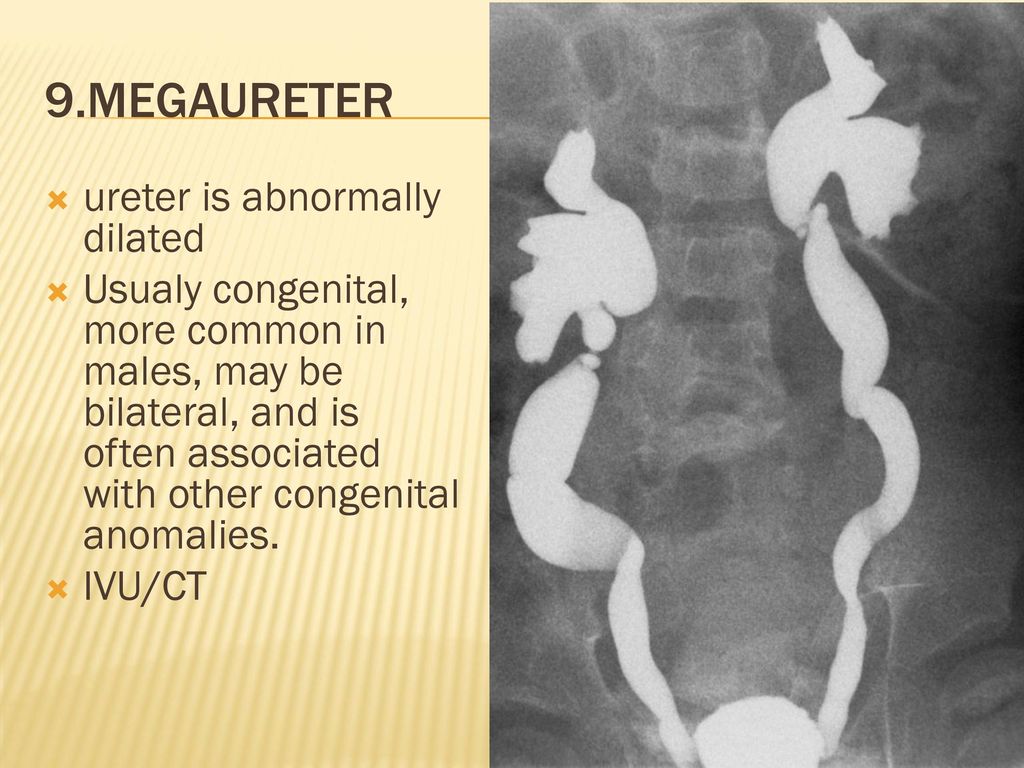

Рефлюксирующий мегауретер: Визуализация и медицинские изображения